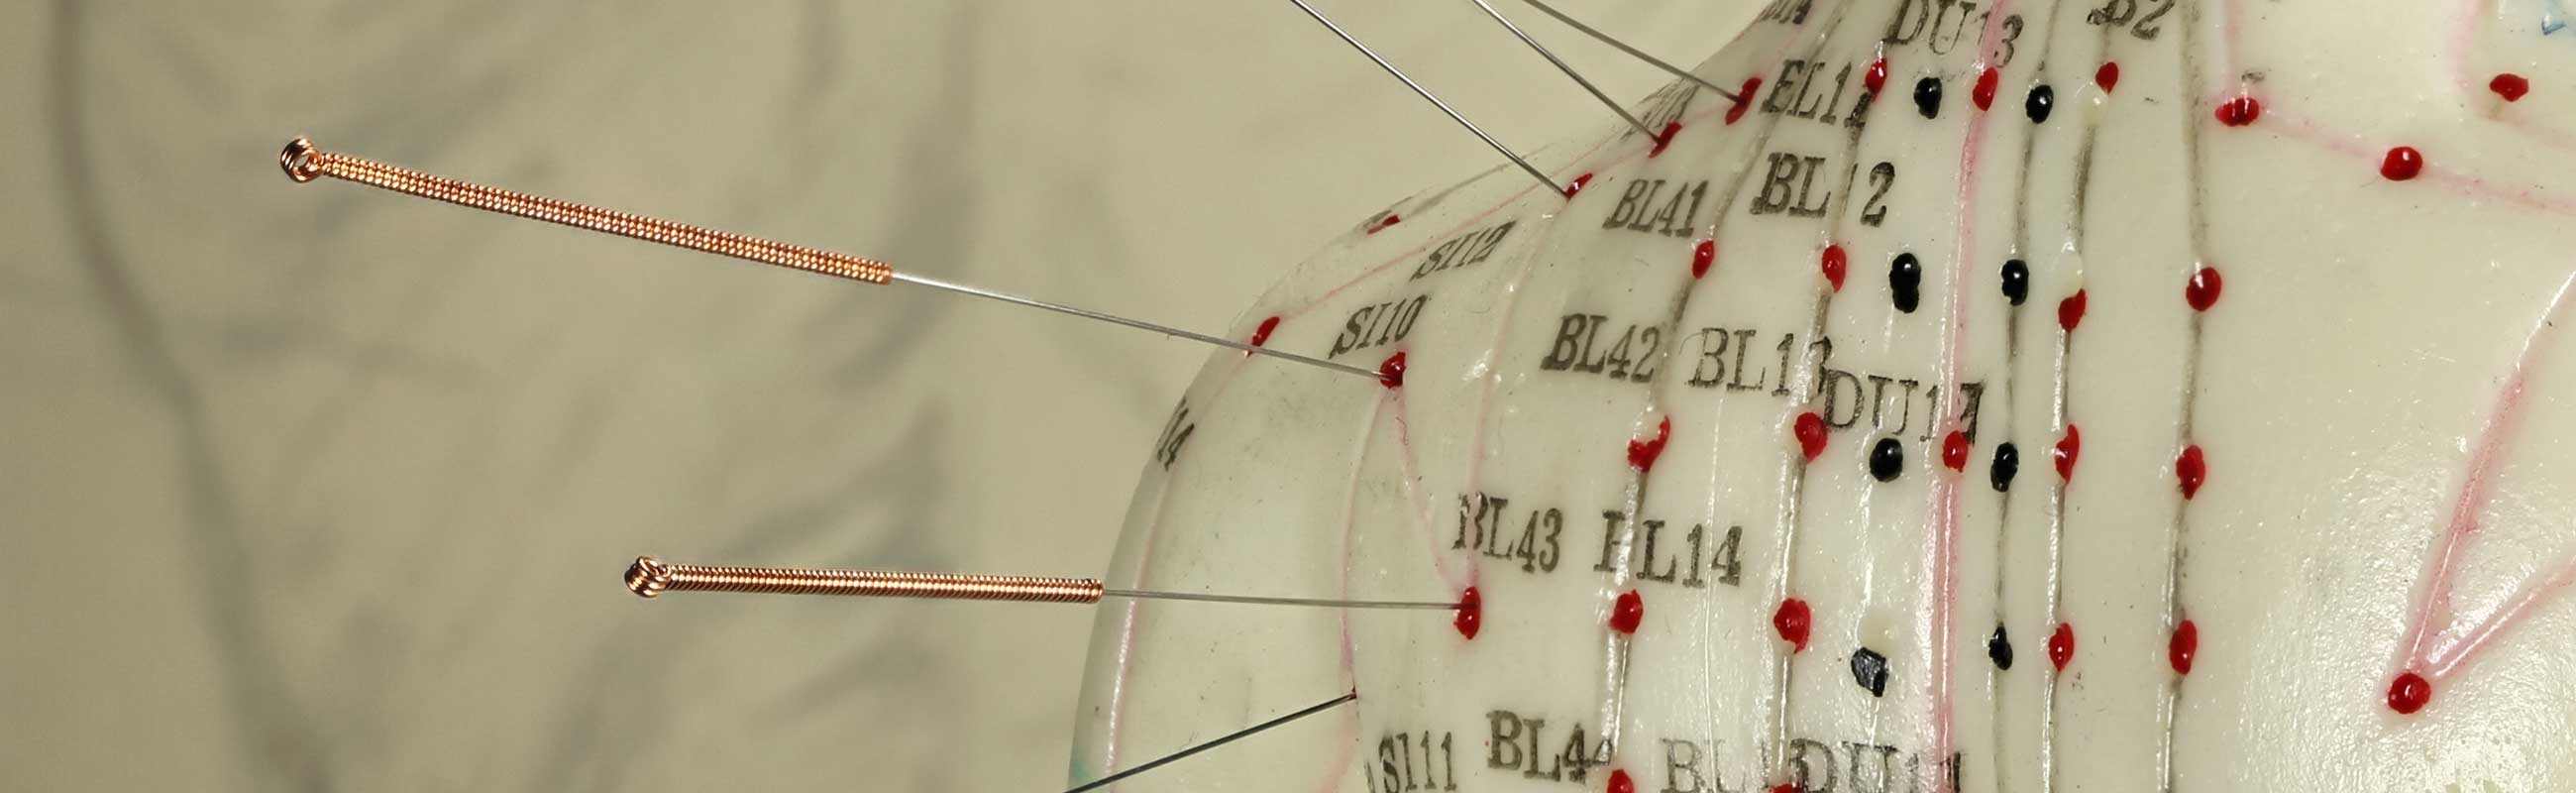

Ob konservative schulmedizinische und operative Behandlungsmethoden oder unser Blick über den Tellerrand hinaus auf alternative Behandlungen (Akupunktur, Lasertherapie, Magnetfeldtherapie, Behandlung mit Hyaluronsäure ...) - gemeinsam finden wir den Weg zum optimalen Behandlungsergebnis.